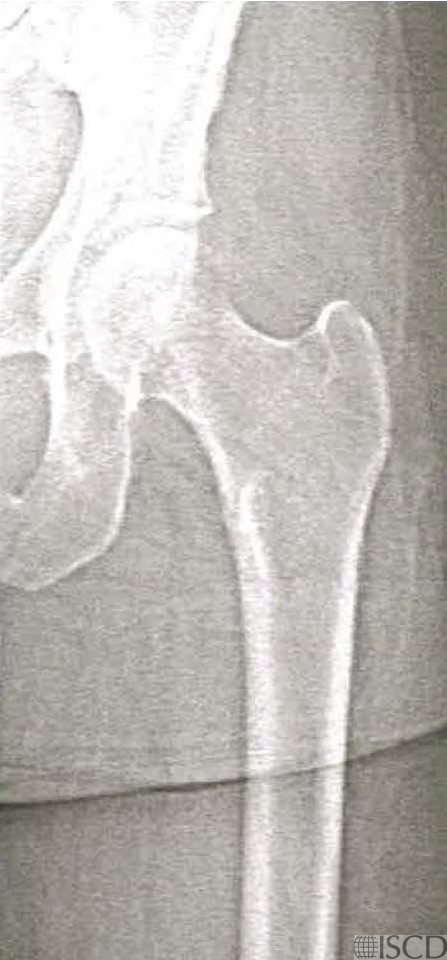

This image shows a scan with an extended length of hip scan, done on the same patient within minutes after the scan on the left. There is not a difference in bone mineral density between the nonextended and extended hip scans, using the 95% confidence intervals for the institution.

This image is the extended hip Hologic scan on the same individual. There is no evidence of a subtrochanteric fracture.

Increasing the length of the femur scan field does not affect proximal hip bone mineral density on both GE/Lunar and Hologic scanners (references below). There is an extended Hologic hip scan that is ordered to look for atypical femoral fractures.